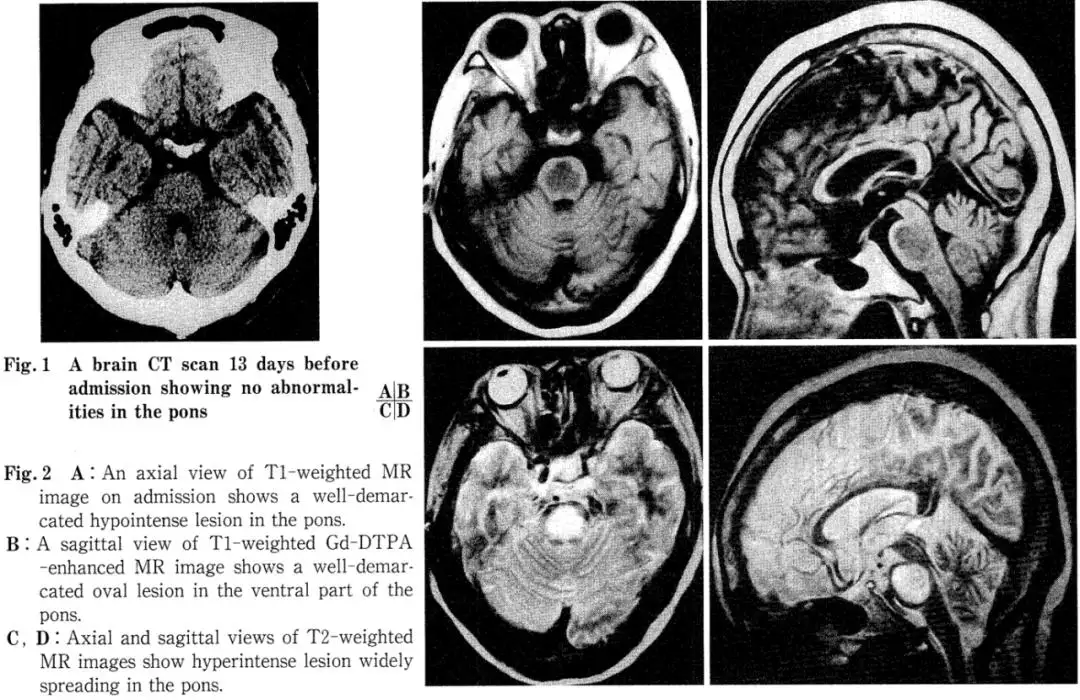

Imaging: A head CT performed at an outside hospital 13 days prior to admission was unremarkable (Fig. 1). However, admission MRI of the brain showed an oval, hypot intense area in the central pons on T1-weighted images, which appeared as a homogeneous hyper-intense lesion on T2-weighted images. This hypot intense area on T1 did not show enhancement after Gadolinium-DTPA administration (Fig. 2A-D). Follow-up MRI at 30 days and 5 months post-admission demonstrated a reduction in lesion size (Fig. 3A, B).

Regarding imaging findings, most reported MRI features of CPM show hypot intensity in the central pons (sparing the tegmentum) on T1 and hyperintensity in the same region on T2. Koch et al. noted that the characteristic MRI feature of CPM is an oval-shaped lesion in the sagittal plane, typically sparing the pontine tegmentum and ventrolateral areas. In our case, the tegmentum and corticospinal tracts were also spared.

Furthermore, Thompson et al. suggest that as myelin lipid protons do not significantly affect MRI signal, acute demyelination alone may not cause the observed changes. The signal alterations are primarily attributed to edema. These changes may evolve into gliosis in the chronic phase, partly explaining the minimal changes on follow-up MRIs in some cases.

Conversely, sequential MRI often shows that acute-phase lesions rarely shrink or disappear completely, with most persisting for 6 months to 2 years. Miller et al. reported one case where the pontine abnormality decreased in size after six months, while another showed no change. In our patient, shrinkage was evident on the one-month follow-up MRI, and the lesion was reduced by more than half after one year. Therefore, long-term MRI observation in CPM is considered to reflect acute-phase edema, subacute-phase demyelination, and chronic-phase gliosis, which is crucial for differential diagnosis. From this perspective, CPM's MRI appearance can mimic cerebral infarction, metastatic or glial tumors, multiple sclerosis, encephalitis, and post-chemoradiation changes. Differentiation from tumors is based on the lack of mass effect; from multiple sclerosis by the larger, solitary lesion; and from infarction by the sparing of corticospinal tracts. However, as Kleinschmidt-DeMasters et al. also reported in 8 autopsy-confirmed asymptomatic CPM cases—all featuring small central pontine lesions—and as Koch et al. emphasized, differentiation from infarction can be most challenging, underscoring the importance of clinical context and sequential MRI observation.

Additionally, while most reported cases, including ours, show no Gd-DTPA enhancement, Koch et al. reported a case with symmetric central pontine lesions demonstrating ring-like peripheral enhancement. They proposed a mechanism similar to that in multiple sclerosis: transient blood-brain barrier disruption at the interface between demyelinated lesions and normal brain. Furthermore, while lesion size often correlates with clinical severity, our patient showed rapid neurological recovery after initiating HBOT despite a large initial lesion sparing only the pontine margins. This is more easily understood if the acute pathology is primarily edema.